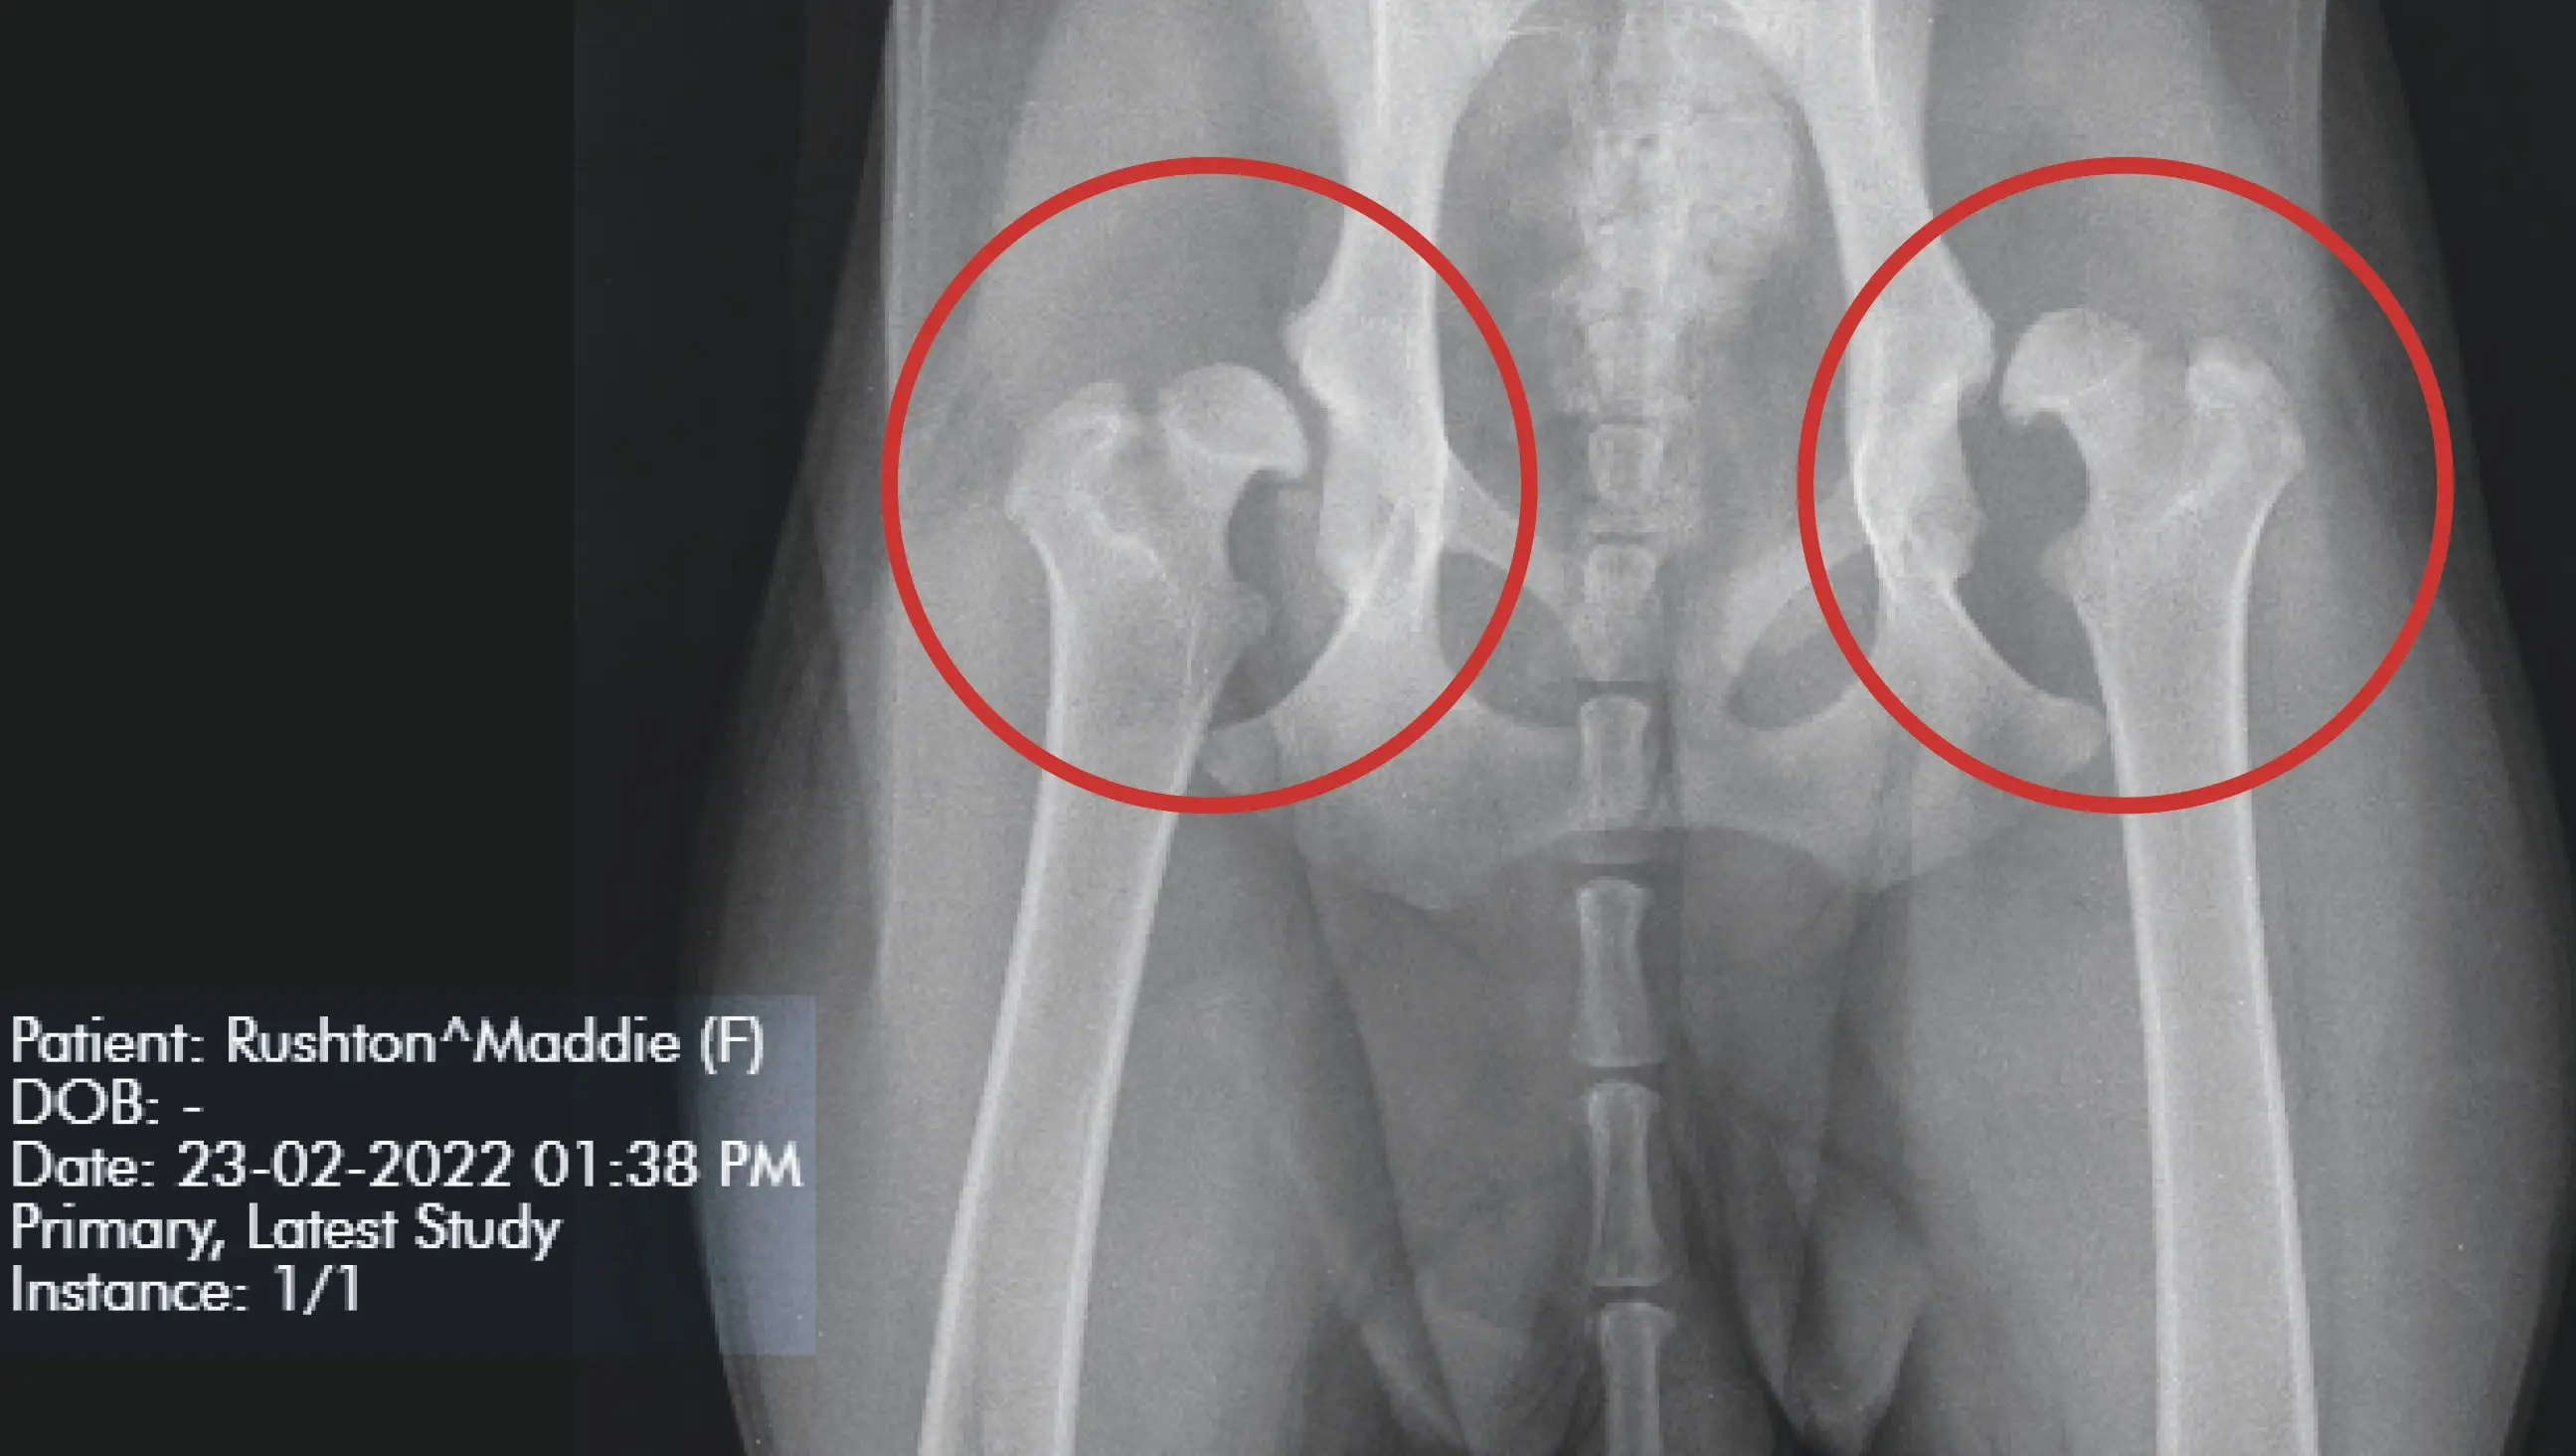

She took the pooch to an orthopaedic referral centre for X-rays, where Maddie was diagnosed with severe hip dysplasia on both sides.

To give her any kind of quality of life, her only option was total hip replacement.

After taking her new pup to the vet in February, it was obvious that Maddie’s hips were in a shocking state and she needed immediate surgery to avoid suffering a huge amount of pain.